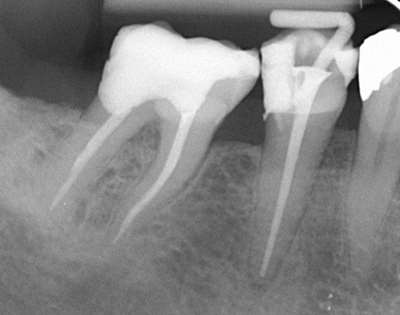

Under en rodbehandling renses rodkanalen og bliver derpå fyldt med et plastisk fyldningsmateriale. Det kan være nødvendigt, at tanden efterfølgende beskyttes af en krone, da rodbehandlede tænder er meget skrøbelige.